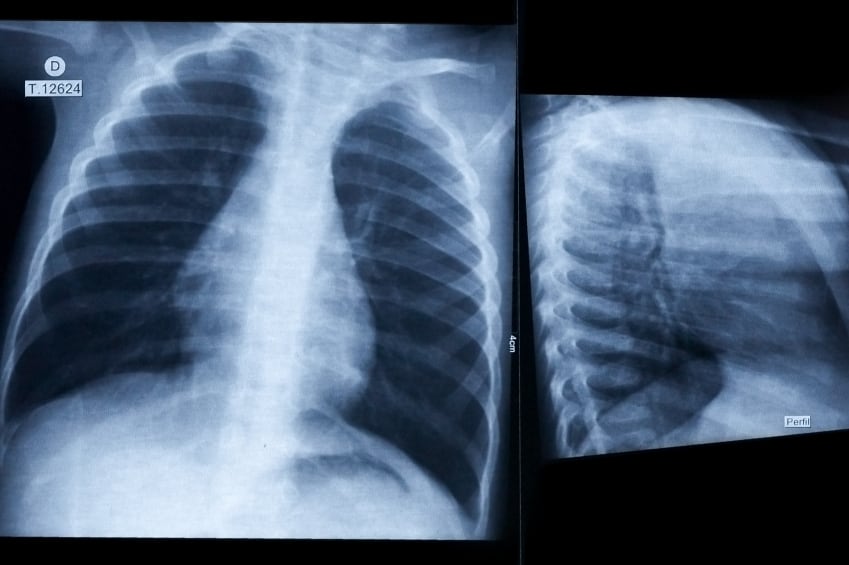

The condition means air passages of the lungs become inflamed and narrowed.

ARI refers to the infection of the sinuses, throat, airways or lungs usually caused by viruses or bacteria. They can be particularly dangerous for people with asthma. According to a 2013 paper, an estimated 11.9 million episodes of severe ARI and three million episodes of very severe ARI in young children resulted in hospital admissions in 2010 globally.